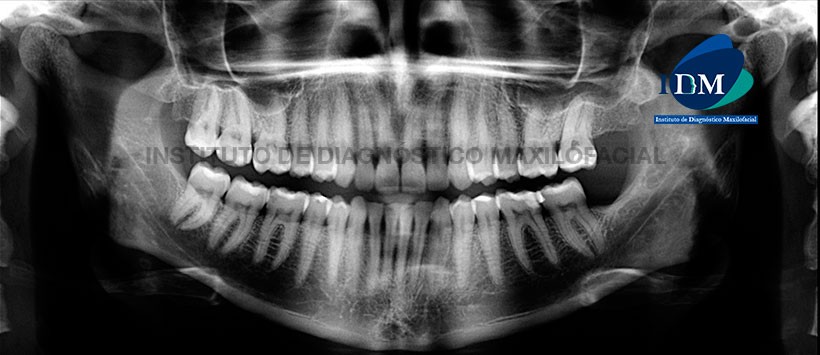

Paciente de sexo femenino (45 años de edad) acude al Instituto de Diagnóstico Maxilofacial por presencia de dolor localizado en la pieza 12. Motivo por el cual se decide hacer un análisis imagenlógico especializado.

A la evaluación panorámica se pudo evidenciar la neumatización alveolar de ambos senos maxilares, apiñamiento dentario del sector anterior y múltiples restauraciones radiopacas. Sin embargo, a la evaluación de la pieza 12, se pudo notar la presencia de un trazo radiolúcido a nivel del tercio medio radicular. (Figura 1)